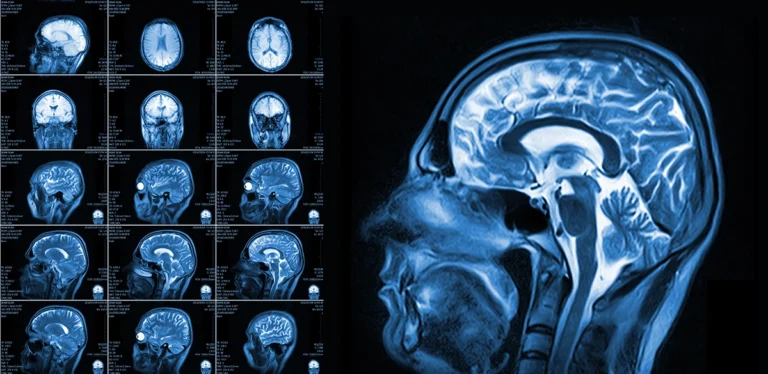

When your provider suspects a stroke, a brain MRI is often one of the first ways they look for clear answers. We’ll explain why brain MRIs are especially useful for finding signs of stroke, how they create detailed images of the brain, and what makes them different from other types of scans.

Brain MRIs use strong magnets and radio waves to create detailed pictures of your brain’s structure. These images can reveal areas that aren’t getting enough blood, as well as spots where bleeding may have occurred.

Different types of MRI settings highlight different brain tissues, making it easier to tell if a stroke has happened, what kind it might be, and how recent it is. This information helps guide decisions about what steps to take next.

Because MRIs can capture images from many different angles and settings, they give a clearer picture of the brain’s condition. That level of detail can make a real difference in identifying subtle signs of stroke.